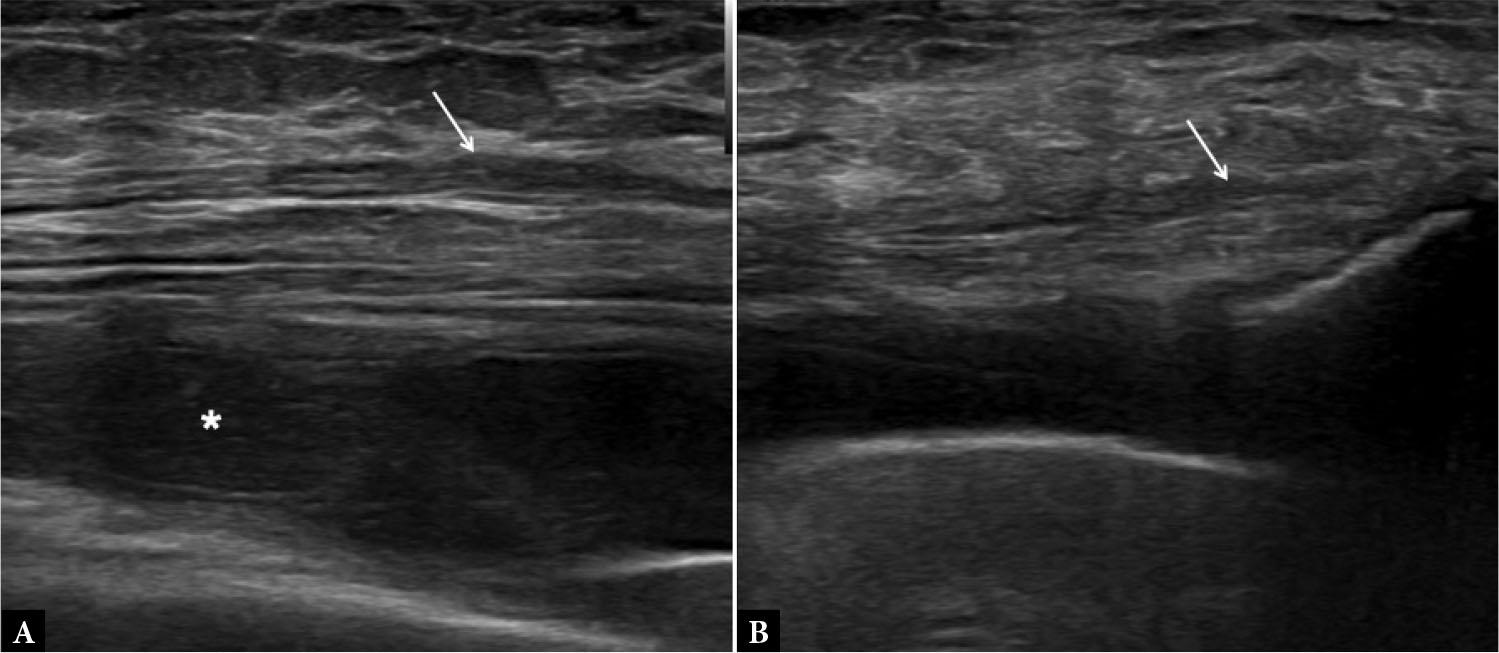

Fig. 3.

Joint effusion. Short-axis US image of the shoulder joint with absent rotator cuff. Central compression (arrow) shows complete compression and displacement of the joint fluid (asterisk)